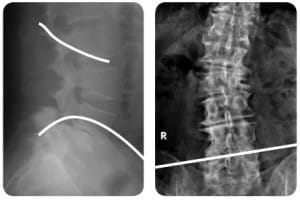

Ver caso real de uso de OLIF en Escoliosis del Adulto Descompensada.

INDICACIONES El Sistema vertebral CLYDESDALE™ está diseñado para su empleo con injerto óseo autólogo a fin de facilitar la fusión intersomática y debe utilizarse con sistemas de fijación complementarios de uso autorizado en la columna lumbar. El Sistema vertebral CLYDESDALE™ está indicado para pacientes con diagnóstico de discopatía degenerativa en uno o dos niveles contiguos desde L2 a S1. Dichos pacientes con discopatía degenerativa pueden presentar también espondilolistesis o retrolistesis con un grado máximo de 1 en los niveles afectados. La discopatía degenerativa se define como una lumbalgia de origen discógeno con degeneración del disco confirmada por la clínica y mediante estudios radiológicos. Está indicado en pacientes con esqueleto maduro que hayan estado al menos seis meses con tratamiento no quirúrgico. Los implantes se pueden realizar a través de un abordaje lateral mínimamente invasivo.